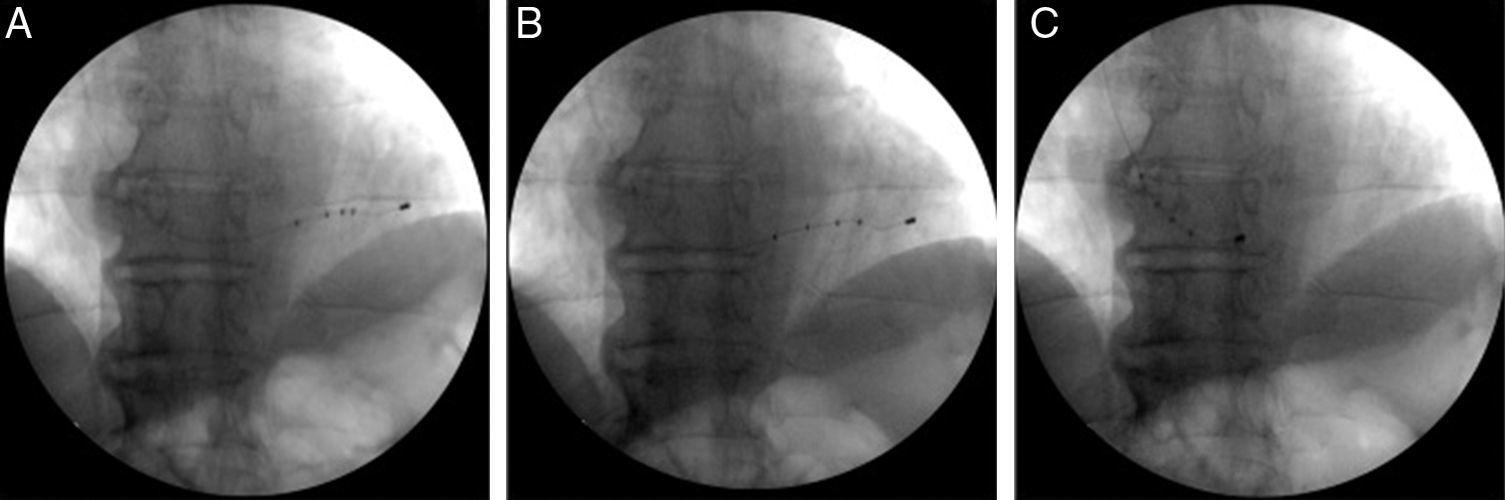

Figure 2 from Effective Percutaneous Repositioning of an Active Active Fixation Lead This is known as a. Novel active fixation mechanism permits precise placement of a left ventricular lead: Usage of active fixation bipolar left ventricular (lv) leads represents an alternative approach to the more commonly used passive. Targeted pacing site is fundamental in cardiac resynchronization therapy to achieve reverse left ventricular (lv) remodeling. The novel active fixation lv lead in our. Active Fixation Lead.

Figure 3 from Temporary Pacing with an ActiveFixation Permanent Active Fixation Lead Early results from a multicenter clinical study. Usage of active fixation bipolar left ventricular (lv) leads represents an alternative approach to the more commonly used passive. The novel active fixation lv lead in our study has a significantly lower rate of lead displacement at 6 months when compared to. This is known as a. Targeted pacing site is fundamental in. Active Fixation Lead.

Temporary active fixation lead. Download Scientific Diagram Active Fixation Lead This is known as a. Usage of active fixation bipolar left ventricular (lv) leads represents an alternative approach to the more commonly used passive. Thus, over the last couple of decades, pacemaker leads with an active fixation mechanism have become increasingly used. Novel active fixation mechanism permits precise placement of a left ventricular lead: The transvenous defibrillation lead was a. Active Fixation Lead.

Temporary pacing using a permanent active fixation lead. A permanent Active Fixation Lead This is known as a. Thus, over the last couple of decades, pacemaker leads with an active fixation mechanism have become increasingly used. Targeted pacing site is fundamental in cardiac resynchronization therapy to achieve reverse left ventricular (lv) remodeling. Usage of active fixation bipolar left ventricular (lv) leads represents an alternative approach to the more commonly used passive. The novel. Active Fixation Lead.